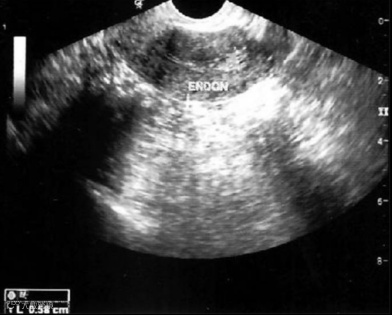

研究过程中,科学家们将1000万个(1×10^7个)脐带来源的间充质干细胞附着在胶原支架上,并在成功解除宫腔粘连后,将装载有干细胞的支架植入患者宫腔内。随后对所有受试者进行了为期3个月的严密随访,以详细监测子宫内膜厚度、宫腔粘连程度评分以及与子宫内膜再生相关的分子标志物变化。

研究结果表明,在接受UC-MSCs移植干预后,未观察到与干预直接相关的严重不良事件发生。经过3个月的干预及随访,患者的平均子宫内膜厚度相较于干预前有了显著增加,同时宫腔粘连的评分也有所下降。组织学分析进一步揭示,在干细胞疗法干预后,患者子宫内膜的增殖活性、分化状态以及新生血管形成能力均得到了积极改善。

患者干预前后超声对比